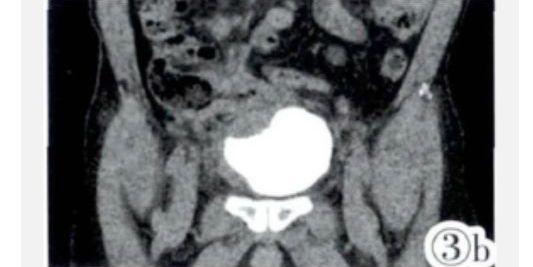

图3a,3b CTU重组示受累回肠与膀胱紧密相连,膀胱右侧壁、膀胱底受压变形。